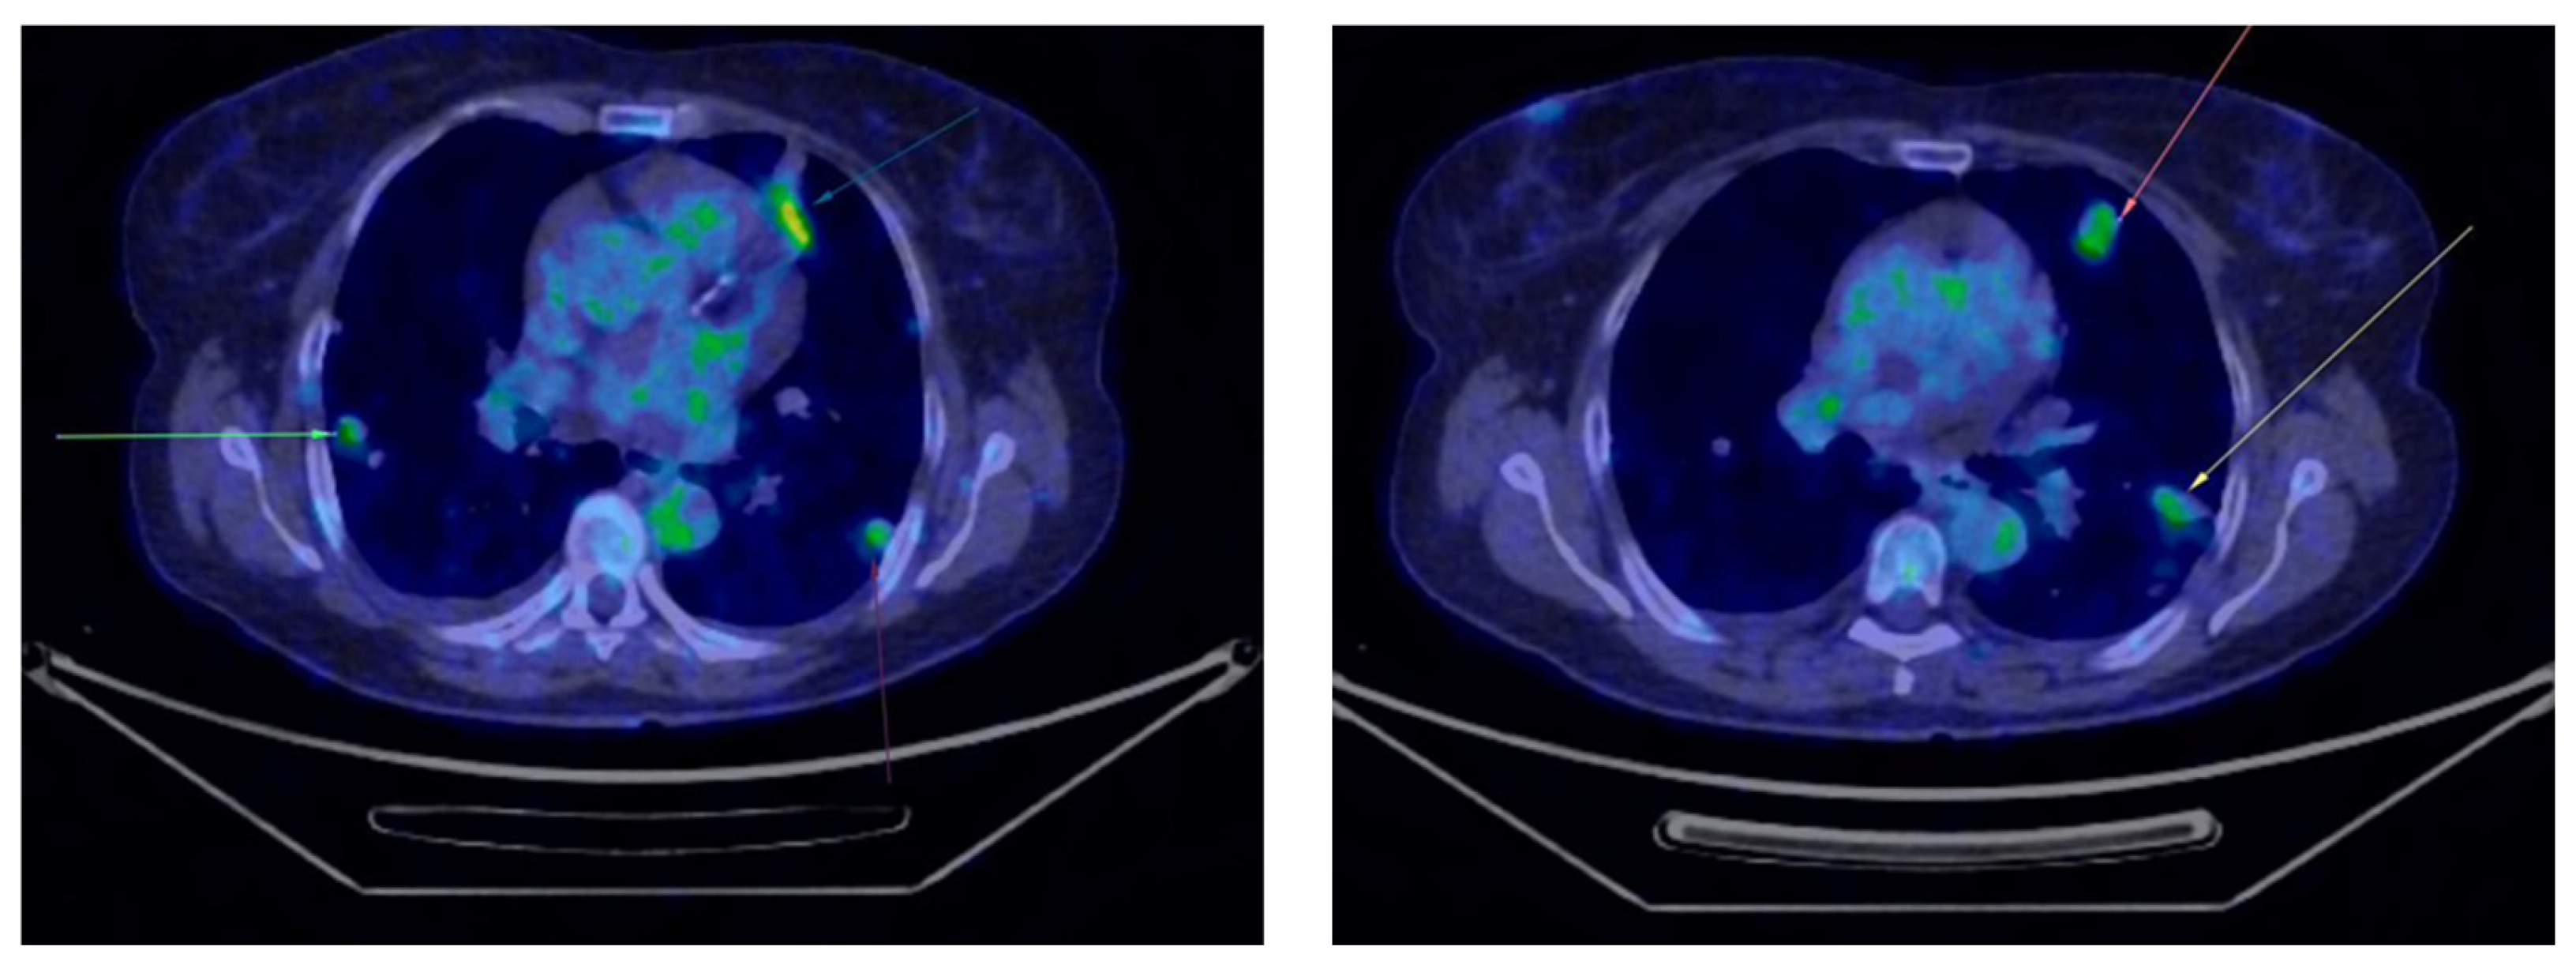

Five month later, the patient underwent her first follow-up PET-CT, which revealed multiple bilateral non-calcified pulmonary nodules, most of which showed minimal uptake, raising suspicion of secondary metastases (Figure 2). In the follow-up PET-CT performed six months later, multiple non-calcified nodules were observed bilaterally in the pulmonary parenchyma, with progressive dimensional and metabolic increases, the largest measuring 28/20 mm. These nodules were biopsied. The preliminary histopathological examination suggested carcinomatous infiltration, which was confirmed by the final histopathological report as clear cell carcinoma with pulmonary localization, indicative of secondary metastasis (Figure 3).

Figure 3.

Second PET-CT scan showing the progression of the lung lesions (marked with arrows).